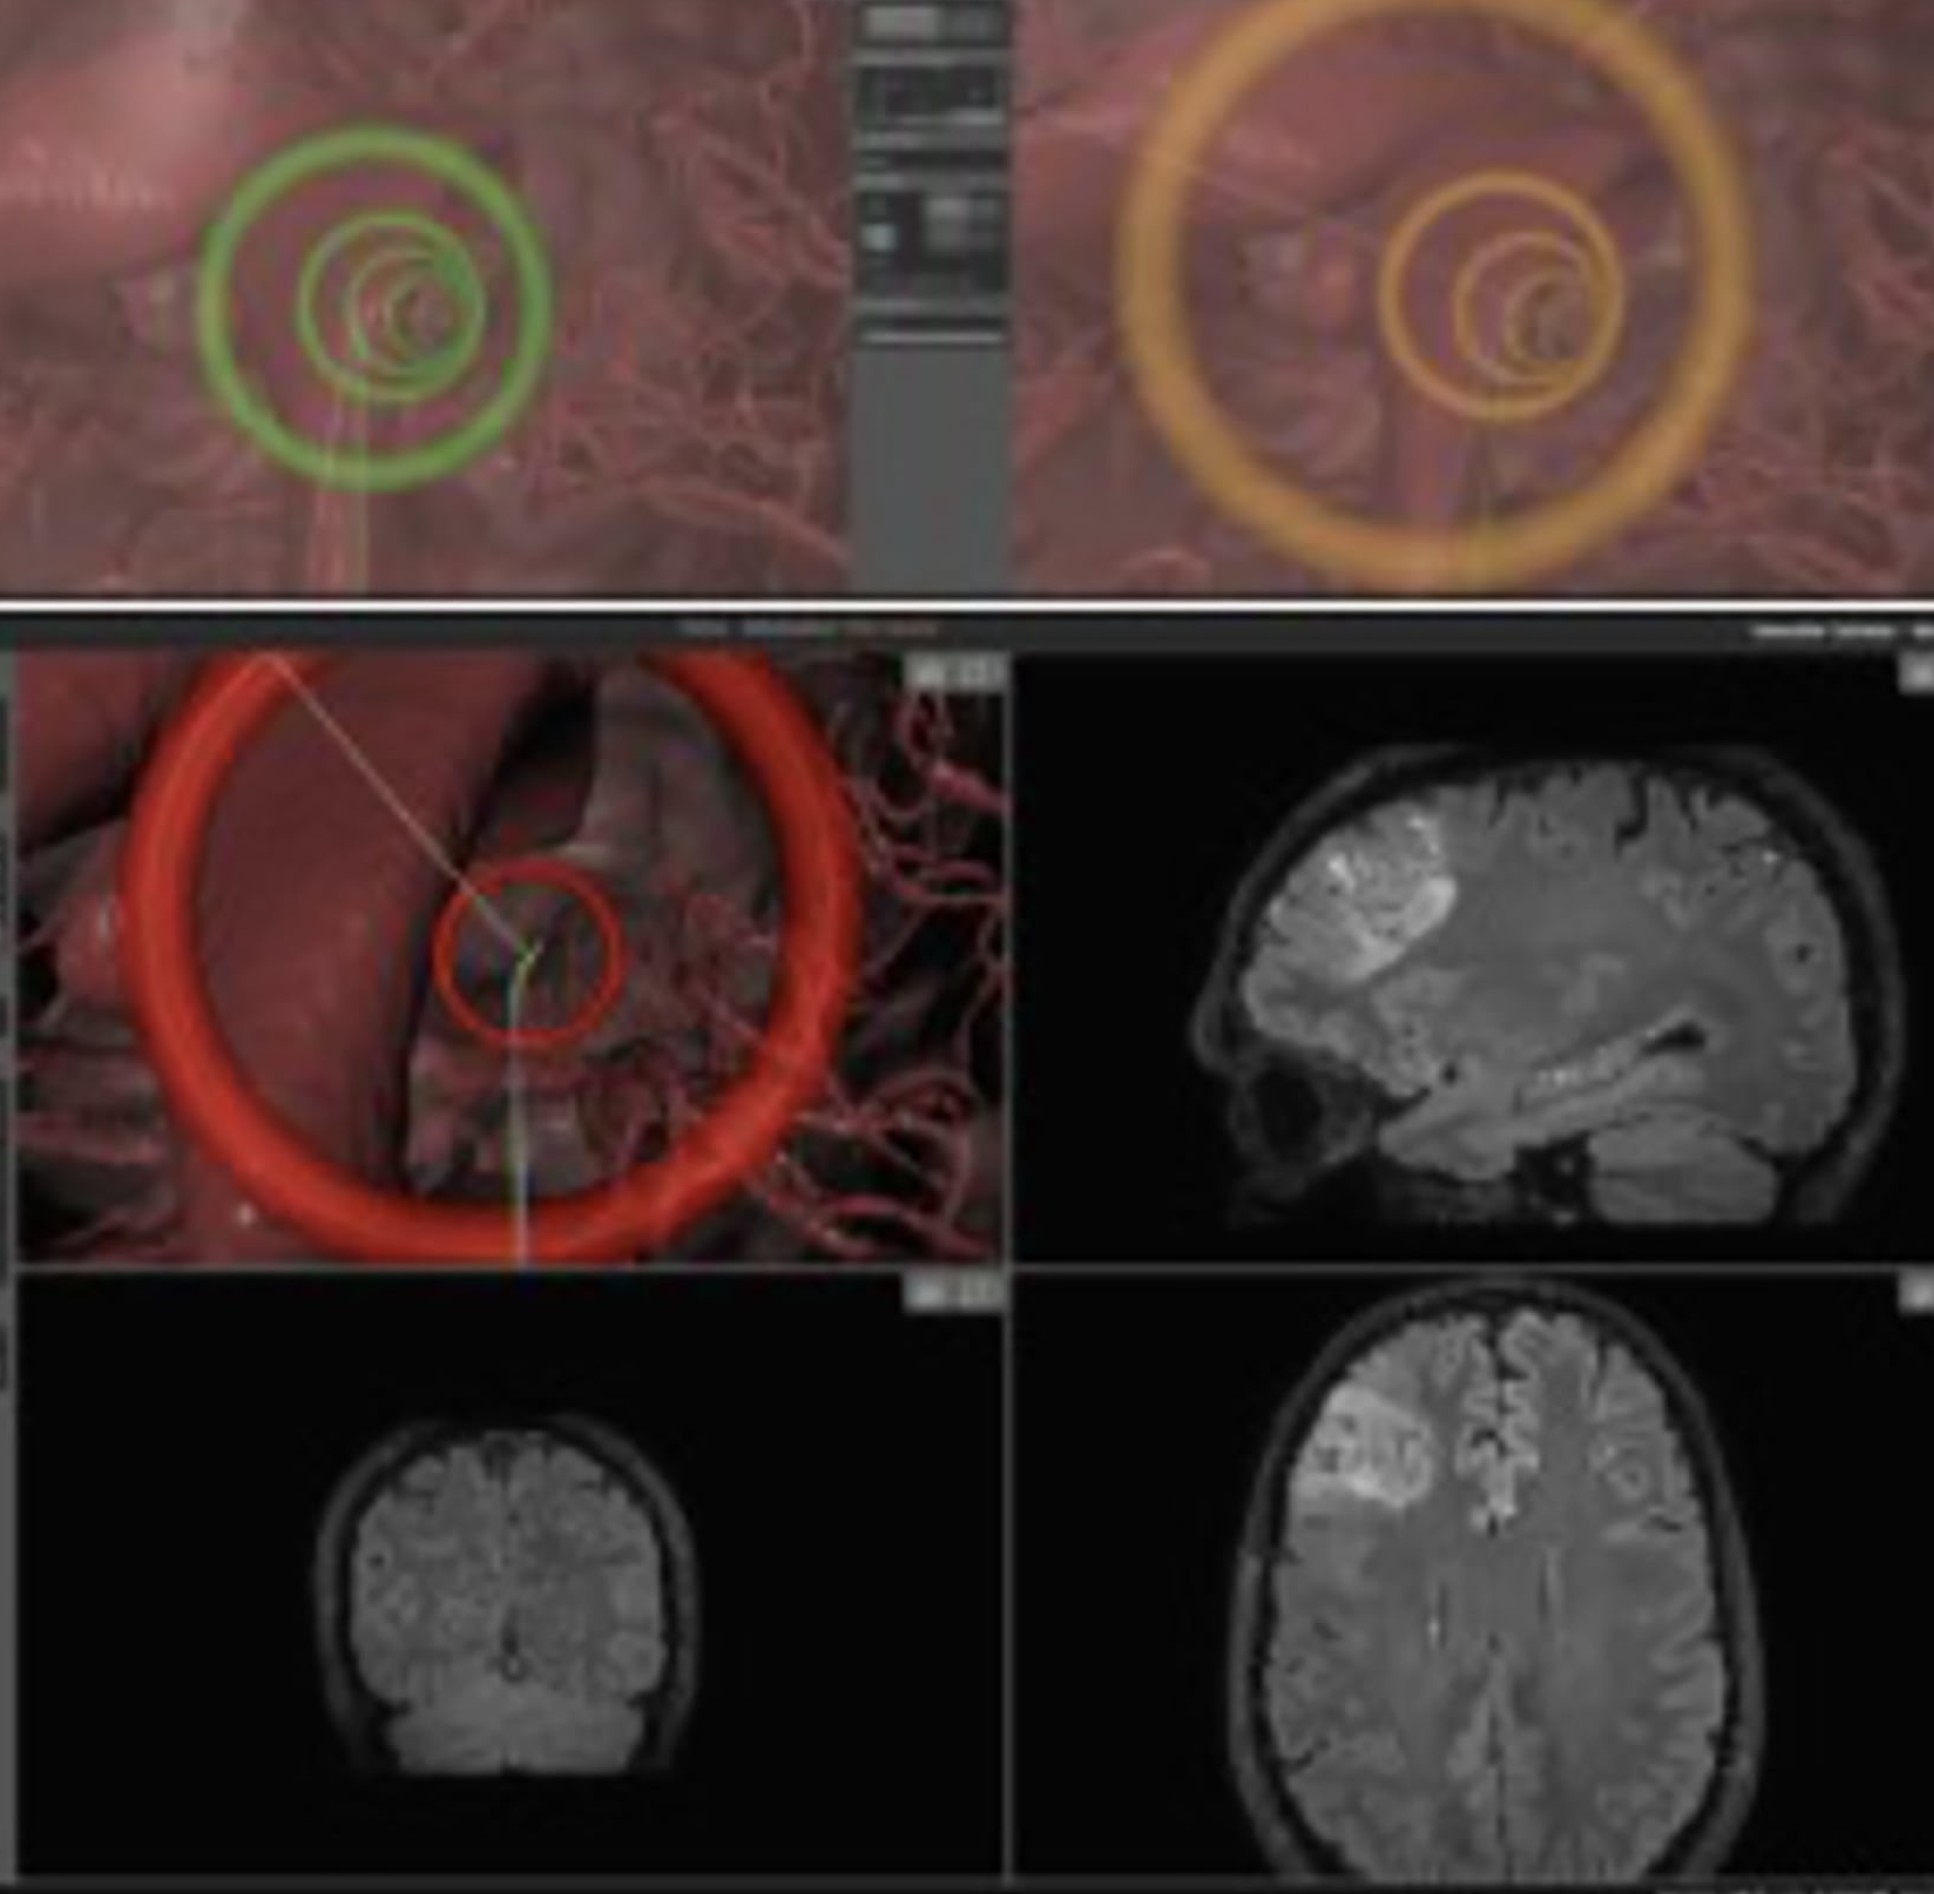

A surgeon's view of the catheter's journey

It includes a soft, flexible catheter to avoid damaging brain tissue while delivering treatment, and an artificial intelligence (AI)-enabled robotic arm to help surgeons navigate the catheter through brain tissue.

It connects to a robotic platform that combines human input and machine learning to carefully steer the catheter to the disease site. Surgeons then deliver optical fibres via the catheter so they can see and navigate the tip along brain tissue via joystick control.

The AI platform learns from the surgeon’s input and contact forces within brain tissues to guide the catheter with pinpoint accuracy.

To test their platform, the researchers deployed the catheter in the brains of two live sheep at the University of Milan’s Veterinary Medicine Campus. The sheep were given pain relief and monitored for 24 hours a day over a week for signs of pain or distress before being euthanised so that researchers could examine the structural impact of the catheter on brain tissue.